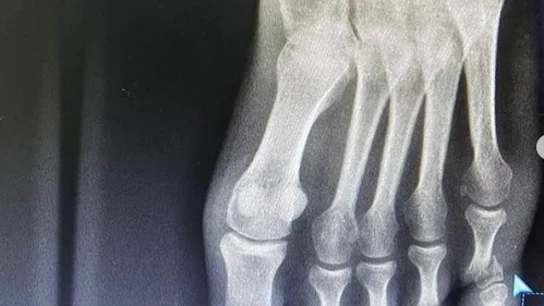

El ciclista lo ha anunciado en sus redes sociales y ha enseñado una radiografía de su pie izquierdo en la que se puede apreciar la fractura.

"Otra fractura para mi palmarés, pero nada nos frena", sentenció el de EF Education Nipo en su cuenta de Instagram, donde mostró la radiografía además de un vídeo.